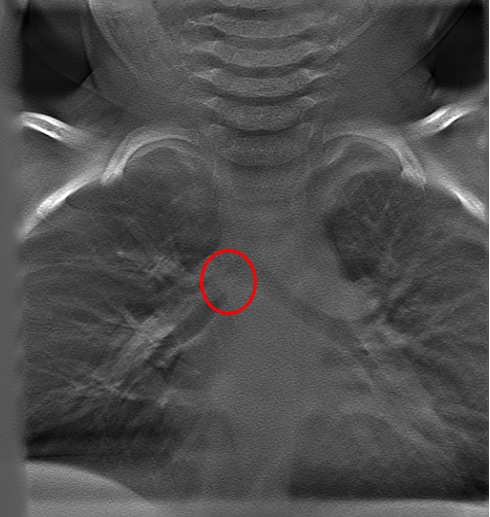

![]() 7岁儿童断层融合提示侧支气管分叉处可见一高密度影 |

![]() 异物为塑料笔头 |